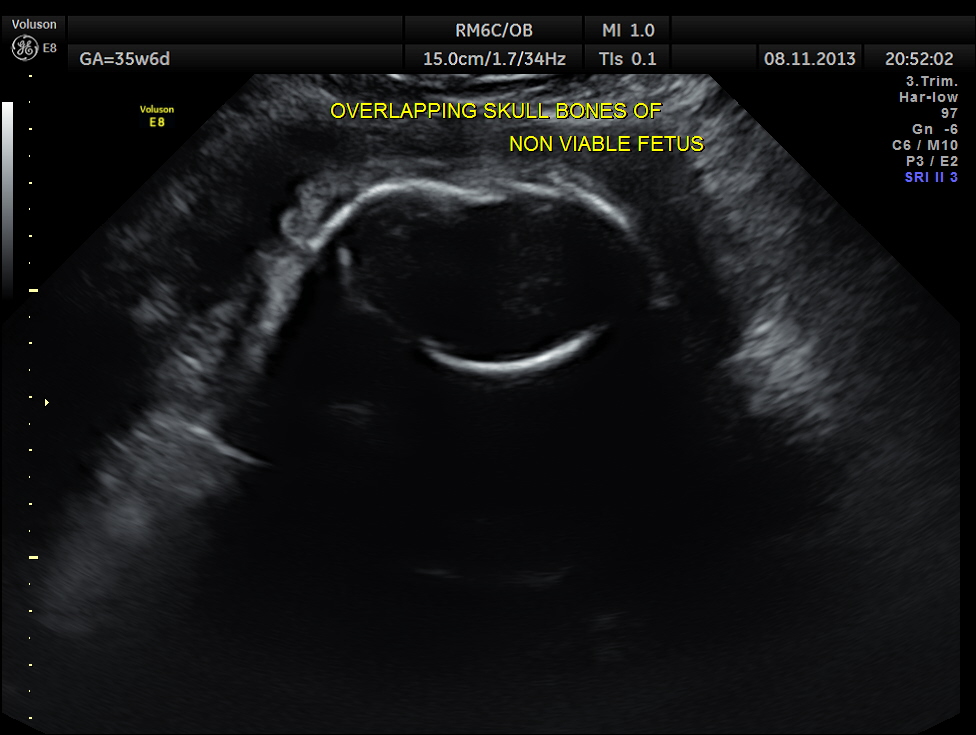

Intra uterine fetal death of the 2nd fetus was seen – Overlapping skull bones and maceration of fetal parts, with absent cardiac activity.

The overlapping skull bones of the fetus ,which died earlier .